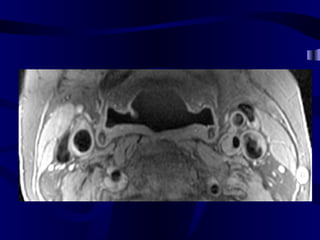

• 74.

Pre and Post-SPIOEnhanced Magnetic Resonance Imaging of ApoE K/O and Wild Type Mice: We used 4.7 tesla MRI unit in our study. After baseline MR imaging with respiratory gating, we injected 1mMolFe/kg super paramagnetic iron oxide to six ApoE deficient and two C57bl mice through the tail vein. Post-contrast MR imaging were performed in day 5 with the same parameters (TR=2.5 sec, TE=0.012 sec, FOV=6.6 cm, slice thickness=2.0mm, flip angle (orient)=trans, and matrices=256x256). We selected the aorta at the level of kidney for comparison of the baseline and post-contrast images.

Apo E deficientmice MRI SPIO experiment

MR Image ofAbdominal Aorta After SPIO Injection in Mouse Apo E deficient mouse C57B1 (control) mouse Before Injection After Injection (5 Days ) Dark (negatively enhanced) aortic wall, full of iron particles Bright aortic lumen and wall without negative enhancement and no significant number of iron particles